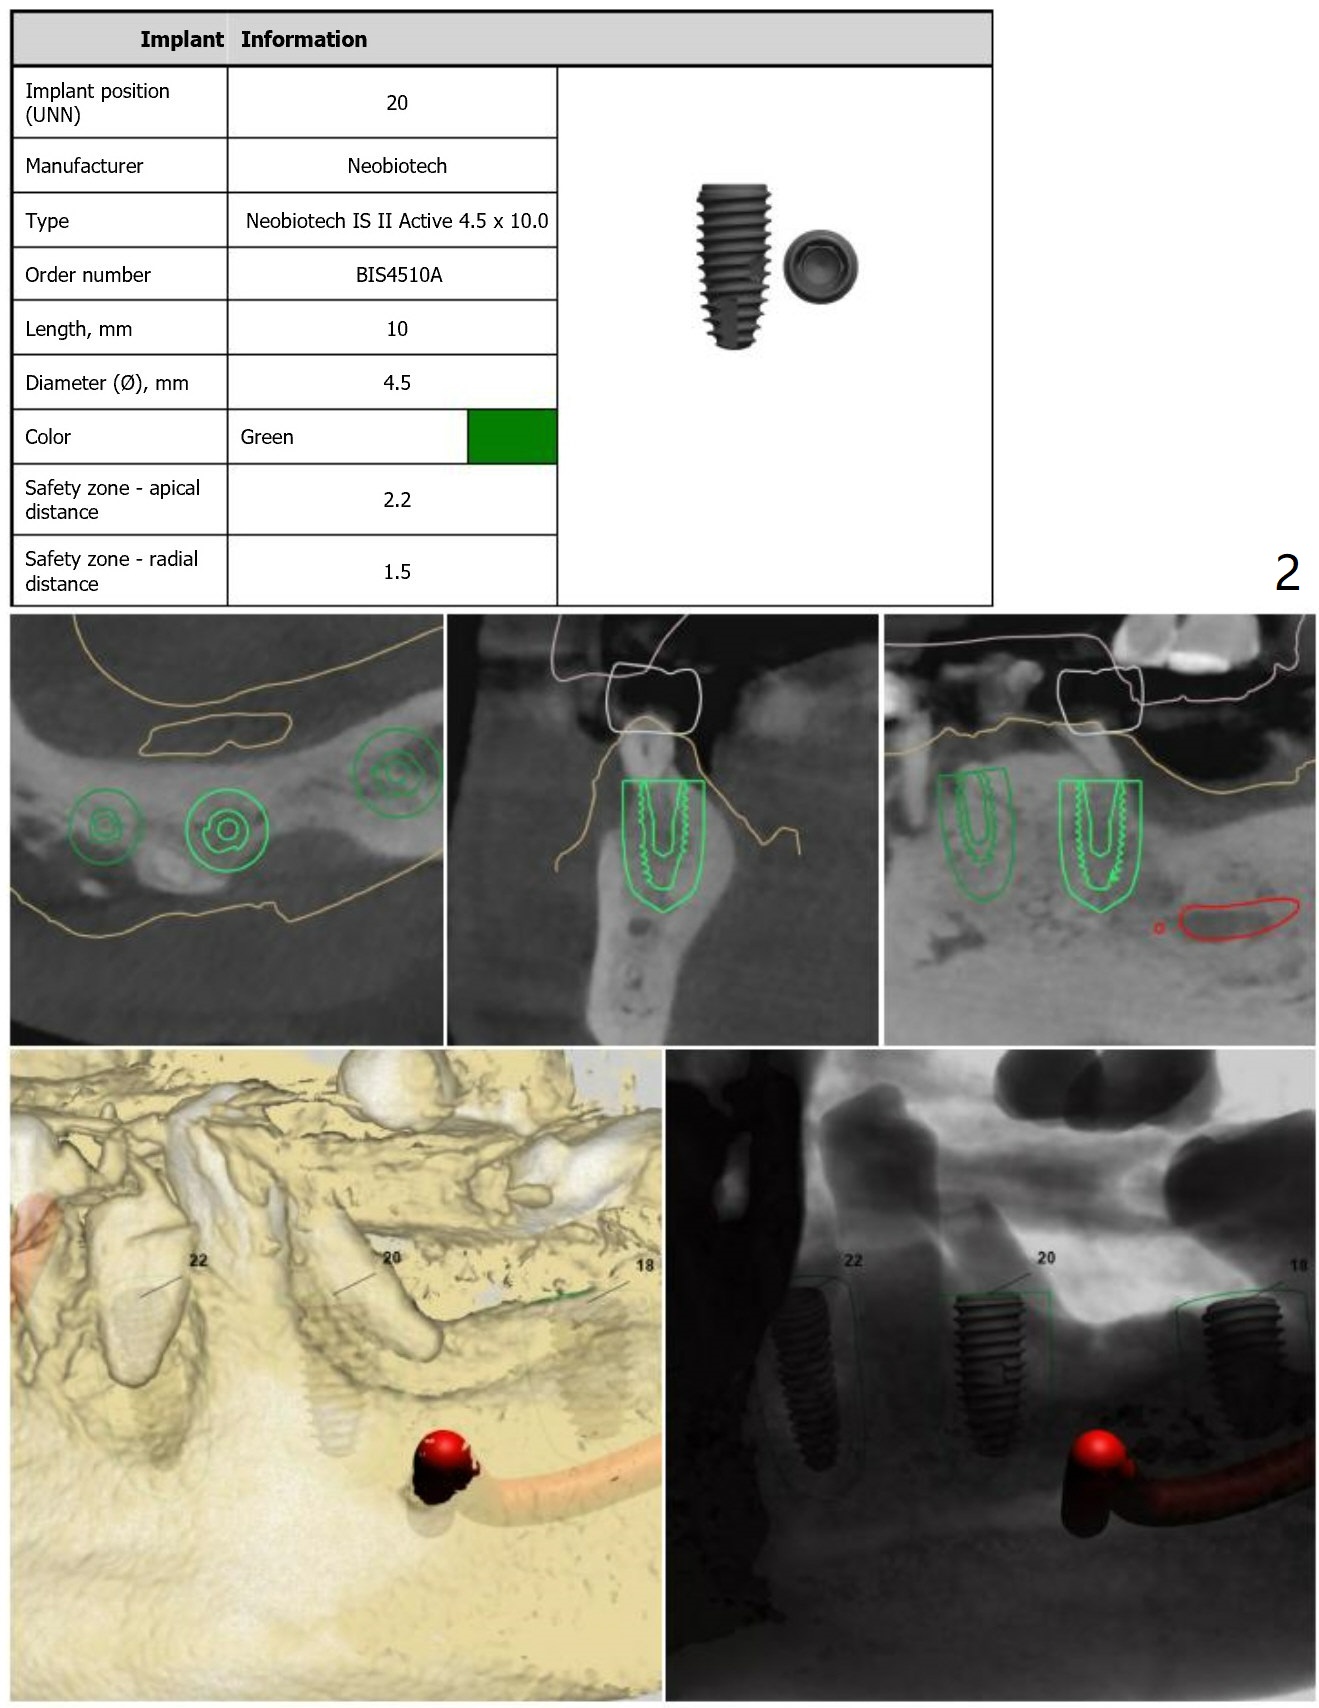

For placement of implants at #20, 22 and 27.

Immediate Implant,